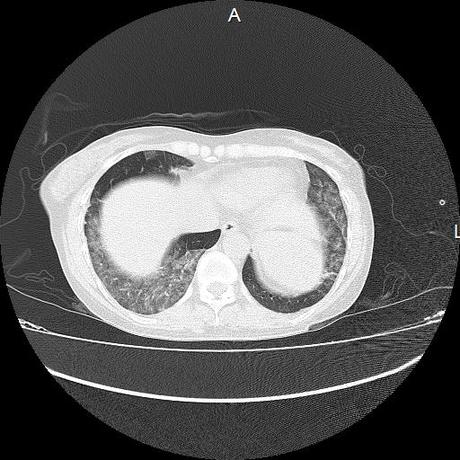

El parénquima pulmonar con areas parcheadas difusas en vidrio despulido combinadas con otras areas hipodensas de baja atenuación debidas a atrapamiento aéreo y engrosamiento intersticial y zonas de fibrosis de predominio en lóbulos medios e inferiores de ambos pulmones.

- LOS HALLAZGOS PUEDEN ESTAR EN RELACIÓN A NEUMOPATIA INTERSTICIAL PROBABLE ETIOLOGIA HIPERSENSITIVA VS AUTOINMUNE/BACTERIANA/FUNGICA.